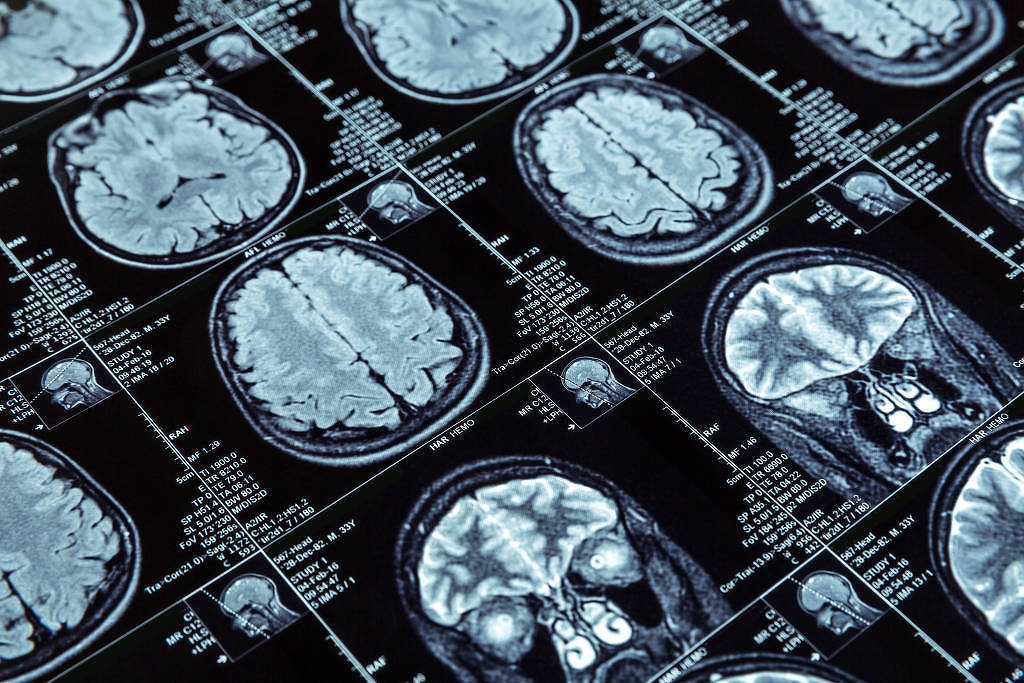

Condições neurológicas, como AVC (Acidente Vascular Cerebral), enxaqueca e Alzheimer afetam hoje 42% da população mundial, segundo um relatório da OMS (Organização Mundial da Saúde) lançado nesta terça-feira (14). O documento alerta para o crescimento preocupante desses diagnósticos, responsáveis por 11,8 milhões de mortes por ano.

Segundo a OMS, distúrbios neurológicos são a principal causa de doenças e incapacidades no mundo, medidos em Dalys (anos de vida ajustados por incapacidade) e anos de vida perdidos. Dados do estudo Carga Global de Doenças, de 2021, mostram que um grupo de 37 condições neurológicas causou, além das 11 milhões de mortes e 3,4 bilhões de casos, 435 milhões de Dalys.

Das 37 analisadas, as dez principais condições relacionadas a óbitos e incapacidades são: AVC, encefalopatia neonatal, enxaqueca, Alzheimer e outras demências, neuropatia diabética, meningite, epilepsia idiopática, complicações neurológicas ligadas ao parto prematuro, TEA (Transtorno do Espectro Autista) e cânceres do sistema nervoso.